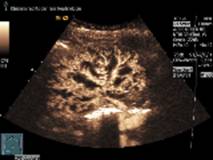

Die bislang eingesetzten Ultraschallmethoden stoßen allerdings an ihre Darstellungsgrenzen, wenn es um die Darstellung der feinen Blutgefäße in der Niere geht. Die Kontrastmittel-Sonografie kann hier abhelfen. Dem Patienten wird dabei ein mit kleinsten Bläschen (Mikrobläschen) versetztes Mittel injiziert, dass binnen kurzem die Niere erreicht, dort durch die Blutgefäße fließt, wobei die Mikrobläschen die Ultraschallwellen reflektieren und die Darstellung der Gefäße ermöglichen.

Professor Dr. Thomas Fischer, Leiter des Ultraschallzentrums der Charité Berlin Mitte und DEGUM-Kursleiter der Sektion Radiologie: „Wir können es zunächst in den größeren Gefäßen beobachten. Etwas später durchströmen die Mikrobläschen die kleineren Blutgefäße, sodass wir die durchbluteten von den nicht durchbluteten Bereichen der Niere unterscheiden können.“